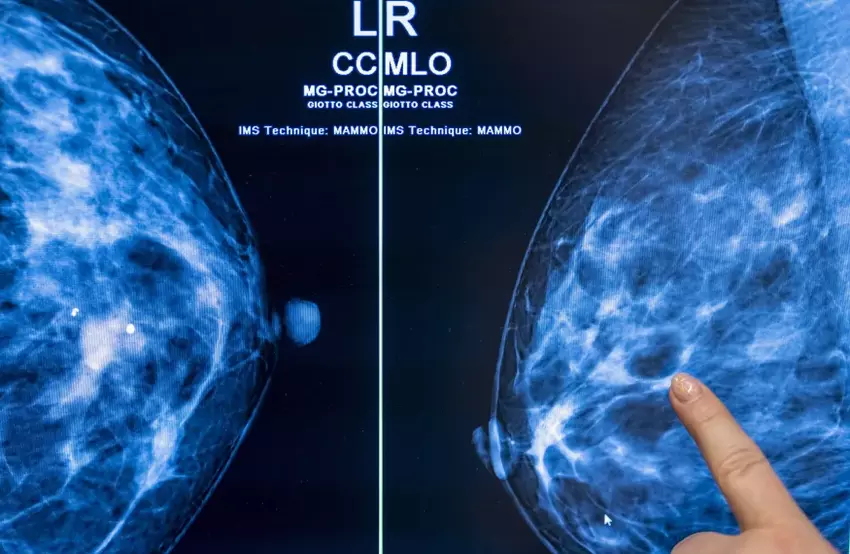

Zastosowanie sztucznej inteligencji w mammograficznych badaniach przesiewowych w kierunku raka może bezpiecznie zmniejszyć obciążenie radiologa o prawie połowę bez ryzyka zwiększenia liczby wyników fałszywie dodatnich.

Badanie przeprowadzone przez zespół naukowców z Uniwersytetu Lund w Szwecji obejmowało obserwację 80 033 kobiet przez nieco ponad rok. Spośród 39 996 pacjentek, które losowo przydzielono do badań przesiewowych w kierunku raka piersi z wykorzystaniem sztucznej inteligencji, u 28% wykryto guzy nowotworowe.

Spośród pozostałych 40 024 pacjentek, które przeszły konwencjonalne badania przesiewowe, raka wykryto tylko w 25% przypadków.

Wskaźnik wyników fałszywie dodatnich zarówno w przypadku AI, jak i konwencjonalnych badań przesiewowych wyniósł 1,5%. Co najważniejsze, radiolodzy pracujący z AI musieli przejrzeć 36 886 mniej badań przesiewowych niż ich koledzy. Zmniejszyło to ich obciążenie pracą o 44%.

"Badania przesiewowe mammograficzne wspomagane sztuczną inteligencją zaowocowały podobnym wskaźnikiem wykrywalności raka w porównaniu do standardowego podwójnego odczytu, przy znacznie mniejszym obciążeniu pracą związaną z odczytem, co wskazuje na bezpieczeństwo stosowania sztucznej inteligencji w badaniach przesiewowych mammografii " - podsumowano badanie.